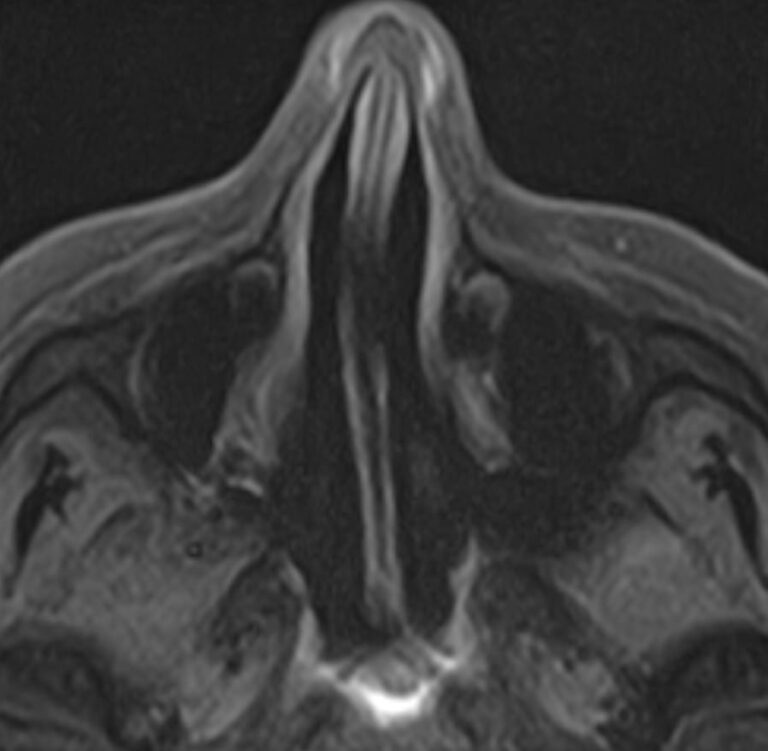

Придаточные пазухи носа представляют собой воздухоносные полости, которые располагаются в костях лицевого и мозгового черепа, выстланы изнутри слизистой оболочкой и сообщаются с полостью носа. МРТ является неинвазивным безопасным информативным способом визуализации данных анатомических областей. Метод позволяет диагностировать различные патологические процессы в области придаточных пазух носа.

Реализацию МРТ пазух носа предписывают, когда другие способы обследования больного не дают полную диагностическую картину. Это необходимо, когда нужны данные о состоянии сложно доступных клиновидных или решетчатых пазух, расположенных за костно-хрящевыми структурами черепа.

Снимки, полученные в ходе магнитно-резонансной томографии, дают подробные данные о:

• патологиях формирования пазух и полости носа;

• аномалиях строения костно-хрящевых структур;

• травмах лицевой части черепа — переломах, смещениях костных фрагментов;

• утолщениях костных стенок и слизистых оболочек;

• кистозных и опухолевых образованиях;

• злокачественных новообразованиях даже на самых начальных стадиях;

• степени симметричности околоносовых полостей;

• скоплении крови или иных жидкостей в придаточных пазухах носа.